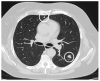

Colorectal cancer is the third-most-diagnosed cancer in males and in females, representing 8% of estimated new cases, and the third cause of cancer-related death in both sexes, accounting for 9% of cancer deaths in men and 8% in women. About 20% of patients diagnosed with CRC present metastatic disease. Although lung metachronous or synchronous metastatic spread without other involved sites has been reported in only a small proportion of patients, considering that this tumor is frequently diagnosed, the clinical approach to CRC pulmonary metastases represents a major issue for thoracic surgeons and CRC oncologists. Among patients diagnosed with pulmonary metastases from CRC, about 9-12% are eligible for local treatments with radical intent, including surgical resection, SBRT (stereotactic body radiation therapy) and ablation therapy. Due to the lack of randomized controlled trials among different local strategies, there is no definitive evidence about the optimal approach, although surgical resection is considered the most effective therapeutic option in this clinical scenario. Oncological achievement of primary radical resection, the biology of primary tumor and metastatic sites, disease free interval and or progression free survival are independent prognostic factors which make it possible to define a cohort of patients which might significantly benefit from pulmonary metastasectomy.